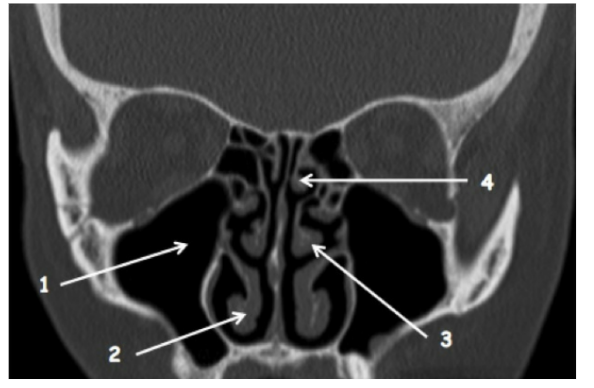

Légnder cette coupe

1 - sinus maxillaire droit

2 - cornet inférieur droit

3 - cornet moyen gauche

4 - cornet supérieur gauche